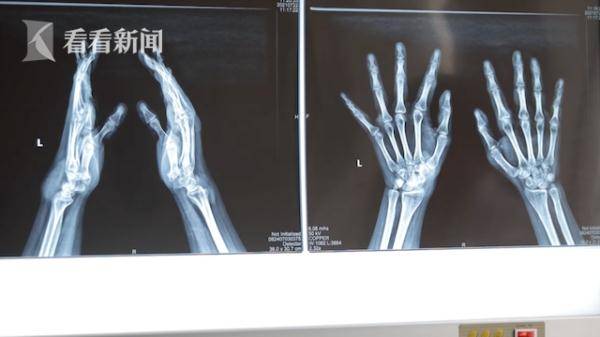

坐落于沈阳的北部战区总医院整形外科的主治医师赵海介绍道:“患者来的时候 , 全身左耳、双手、双足一共有15处痛风石 , 双手10个 , 脚上四个 , 耳朵上一个 , 左腕部最大的能有鸡蛋大小 , 手部最小的能有黄豆大小 。 ”

而小王的行动也受到了病痛的限制 。 他告诉采访采访人员:“除了疼痛外 , 痛风对关节的行动也造成了影响 , 比如说回弯回不过去一碰就疼 , 走路会瘸 。 ”

主治医生表示 , 小王的痛风石如果继续生长 , 很可能破坏骨胳 , 造成不可逆的关节损害 , 必须通过手术切除 。

痛风石形成的根本原因是高尿酸血症 , 当血尿酸过高 , 它就会从血液中析出晶体 , 沉积到关节处 , 随着结晶越来越多 , 逐渐增大 , 就会出现痛风石 。 而冰冻三尺非一日之寒 , 痛风石的形成往往需要几年甚至几十年的时间 , 因此医生分析 , 19岁的小王能长这么多的痛风石 , 这说明他在未成年时就已经患上了高尿酸血症 。